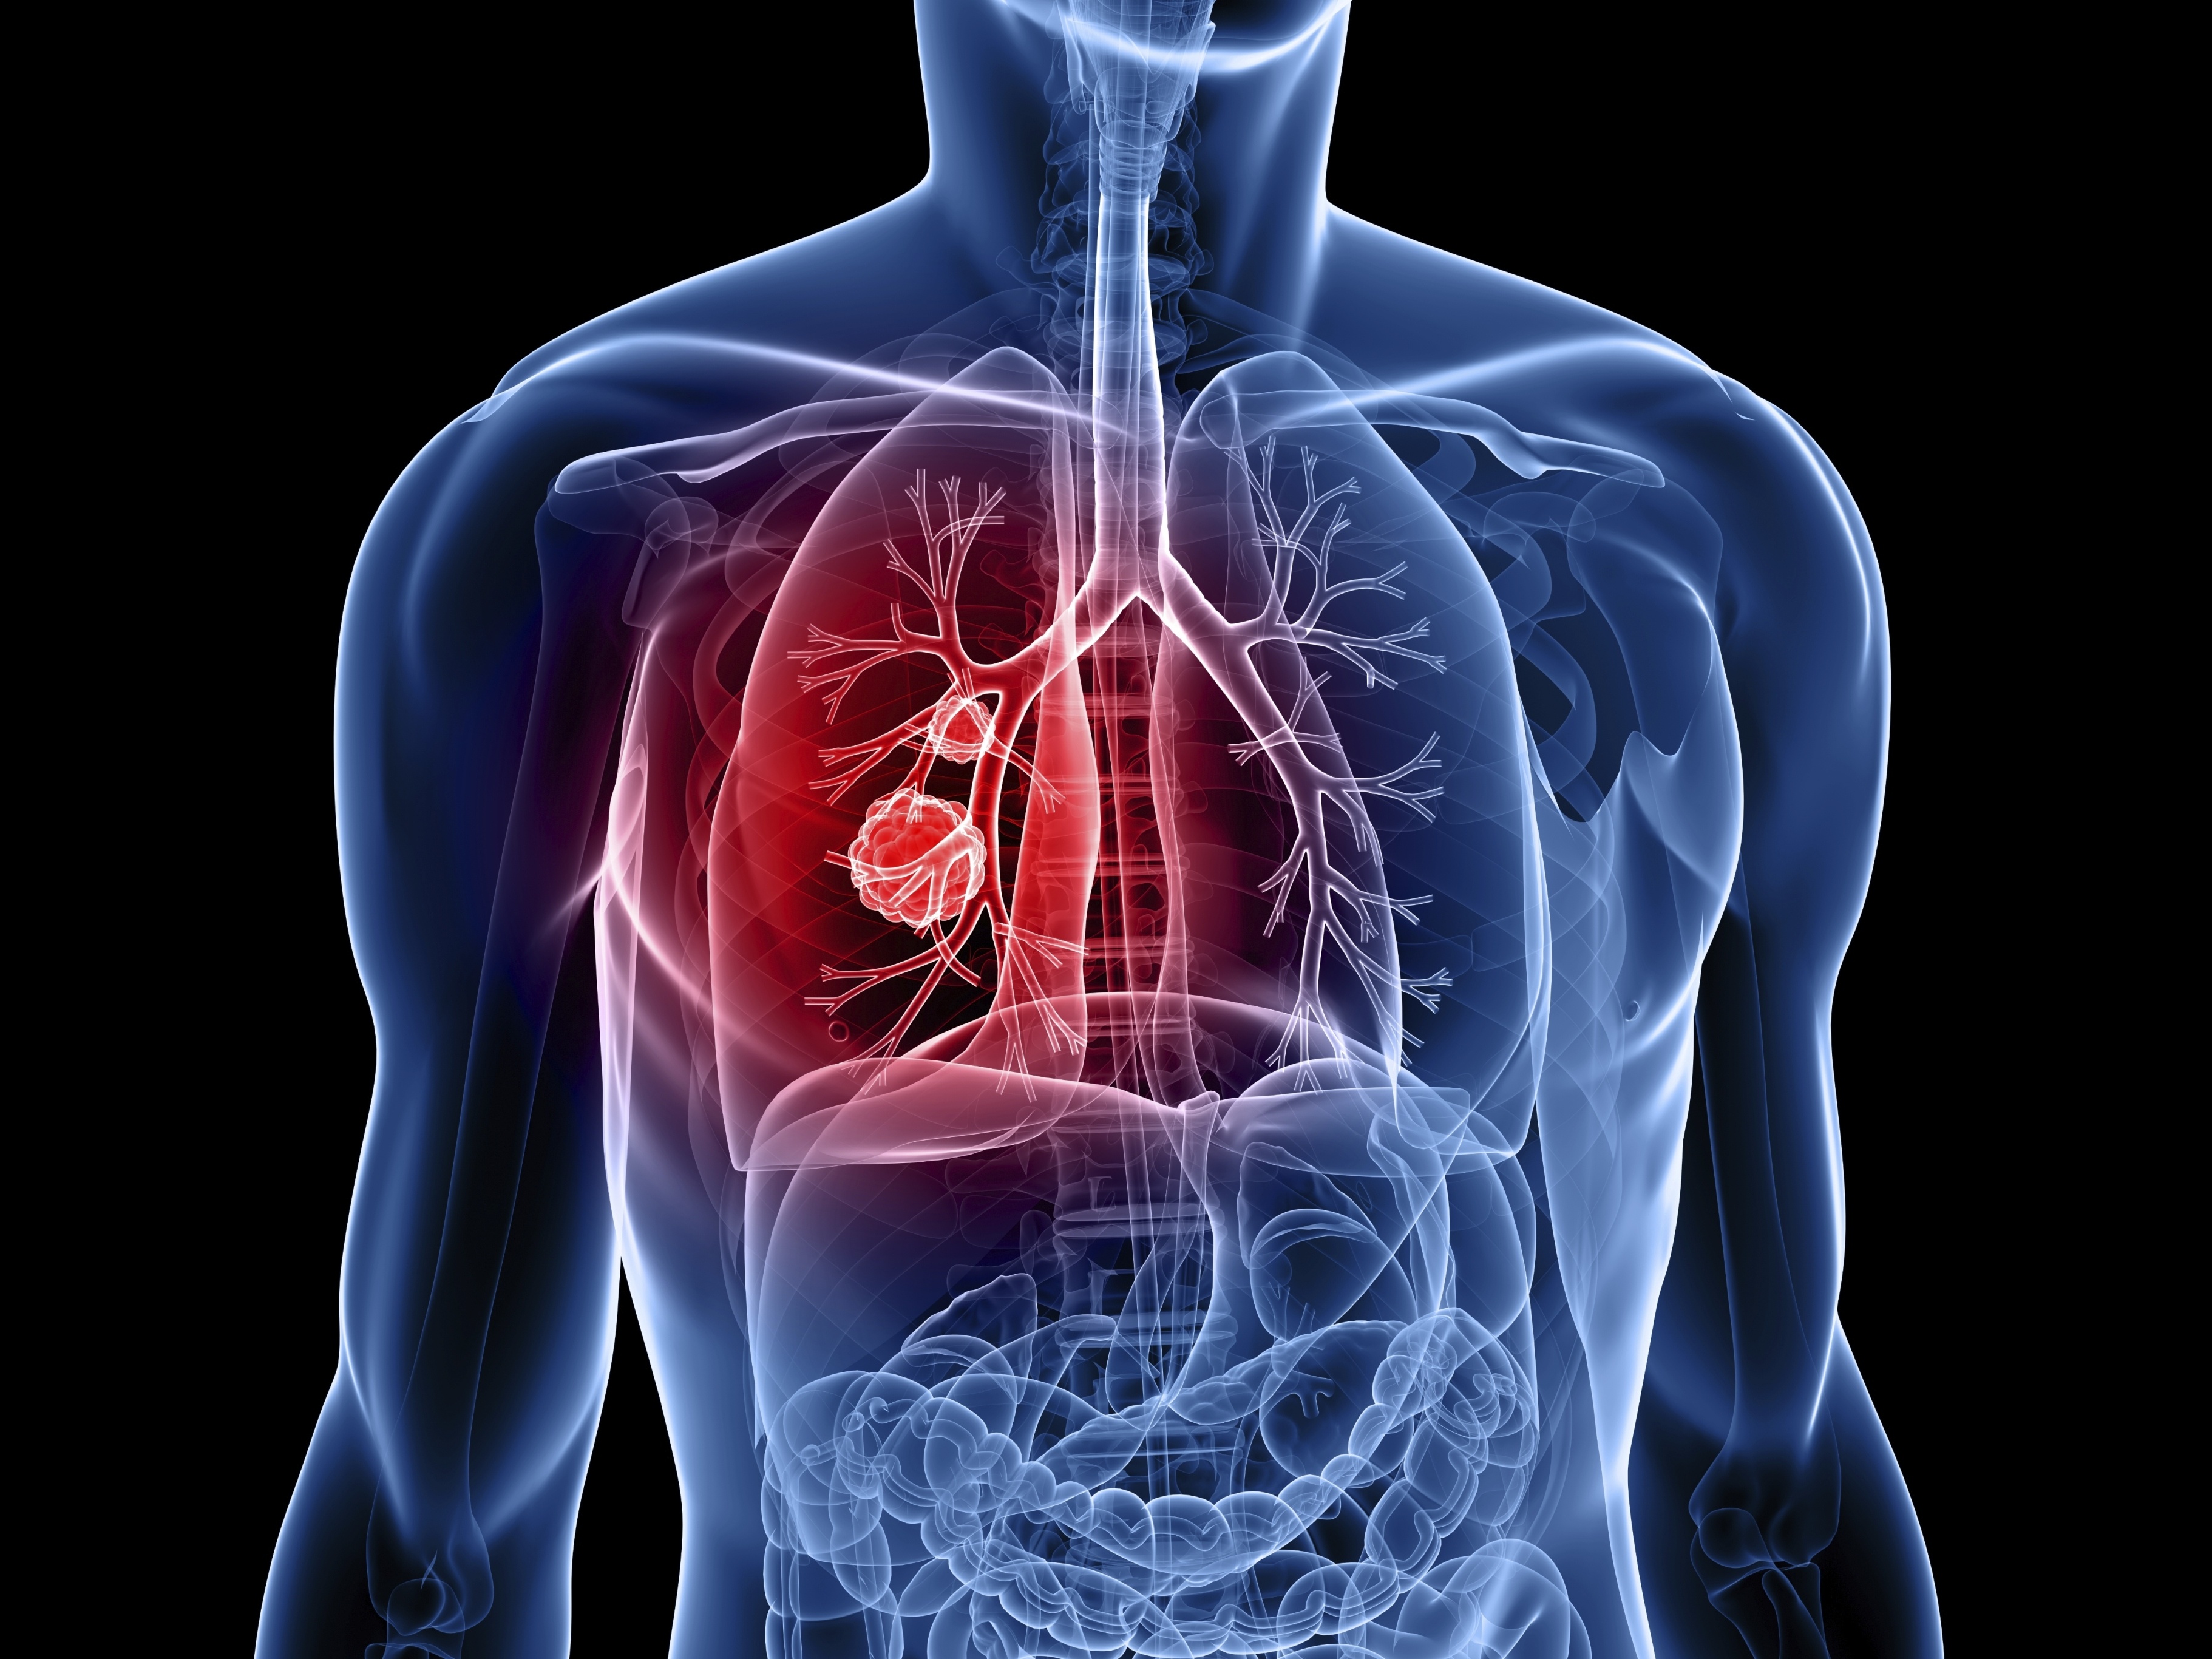

Có mấy loại ung thư phổi? Ảnh: Cancerworld.

Có 2 loại ung thư phổi, loại tế bào nhỏ và loại không phải tế bào nhỏ. Những người hút thuốc lá thường mắc ung thư phổi tế bào nhỏ. Loại này phát triển nhanh, di căn đến các cơ quan khác của cơ thể. |